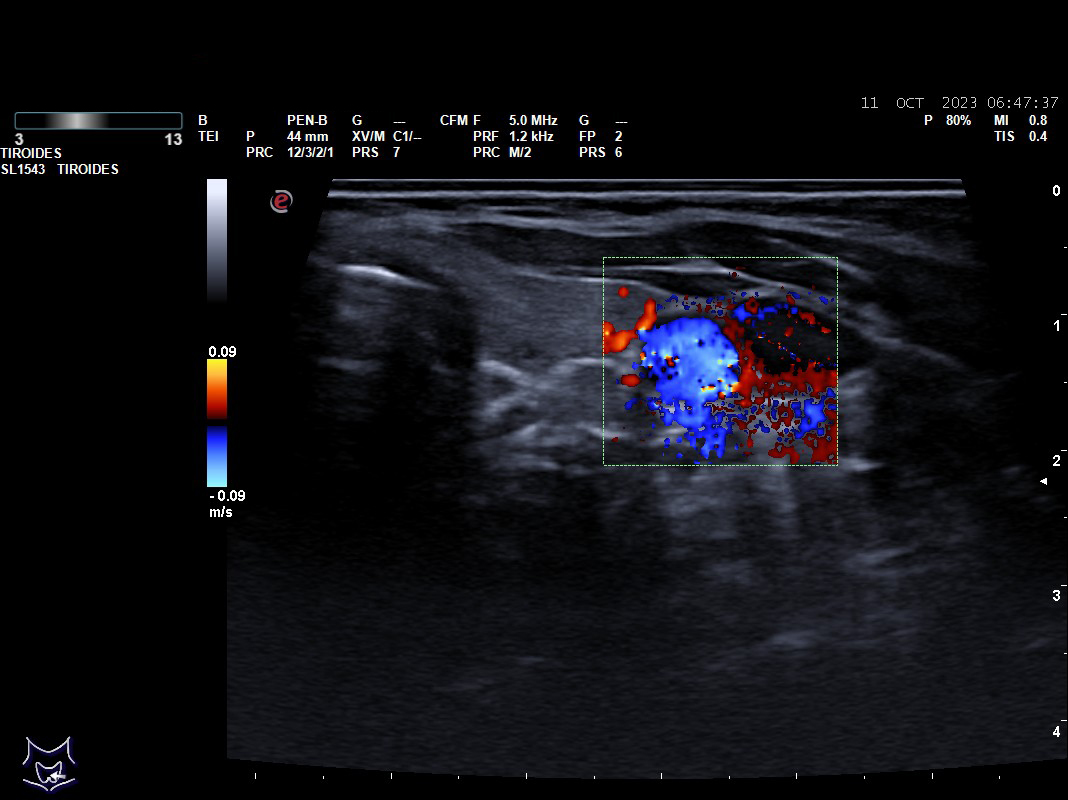

Hallazgos ecográficos: nódulos tiroideos subcentimétricos sin cambios, yugular interna izda con contenido discretamente hiperecogénico que no capta Doppler y colapsabilidad incompleta.

Se deriva a urgencias es valorada por cirugía vascular quienes describen la presencia del trombo sin poder precisar su final y se ingresa a la paciente ya que el servicio de radiología no considera realizar en ese momento el estudio pertinente.

Tras cinco días de ingreso se realiza un ecodoppler reglado descartándose la trombosis venosa, se suspende la anticoagulación y se da de alta sin tratamiento.